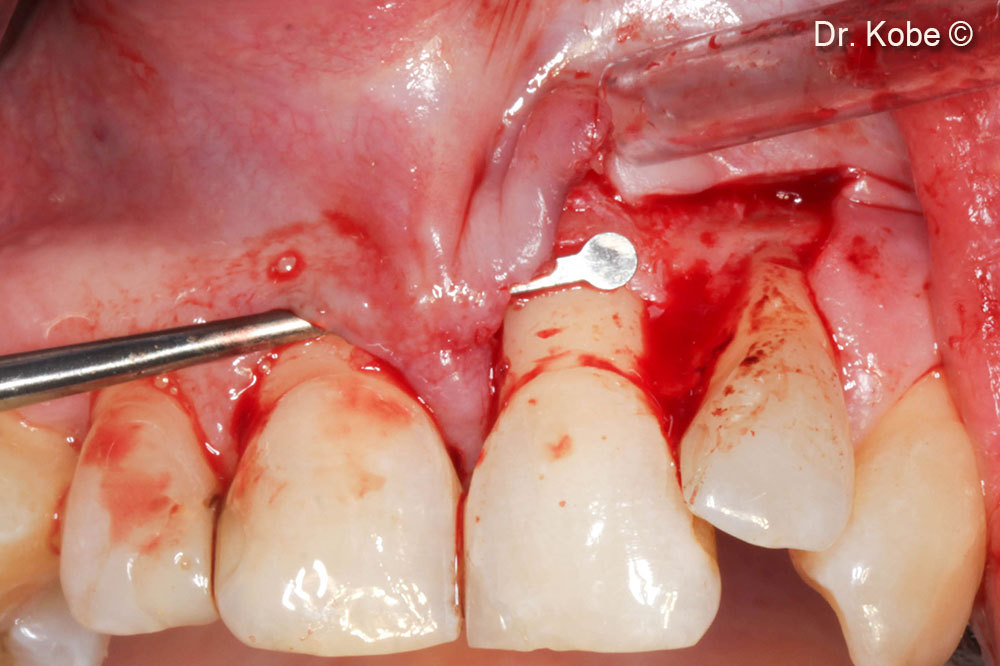

6. Defect filled with OsteoBiol®  Gel 40